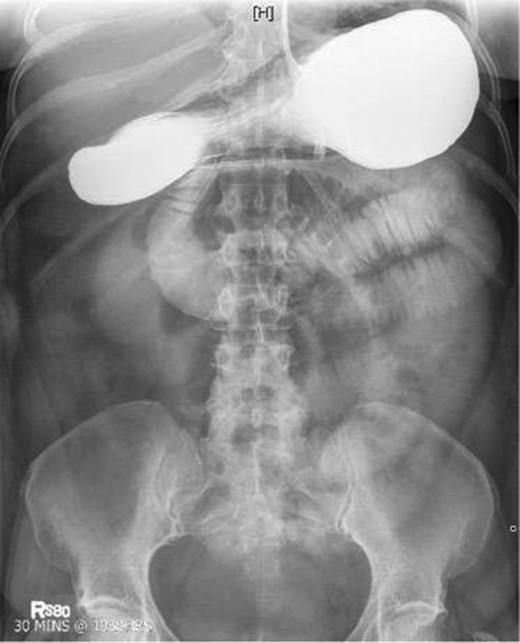

Laboratory studies were remarkable for leukocytosis, and an elevated lactate that improved with hydration (Fig. 1), while urinalysis was unremarkable. Abdominal CT scan obtained at this time demonstrated a partial SBO in the mid-small bowel as well as inflammation and thickening of the duodenum. A small bowel series was ordered, and showed high grade SBO (Figs 2–5).

Fluoroscopic barium study demonstrating oral contrast agent progression through the small bowel at 30 min after ingestion.